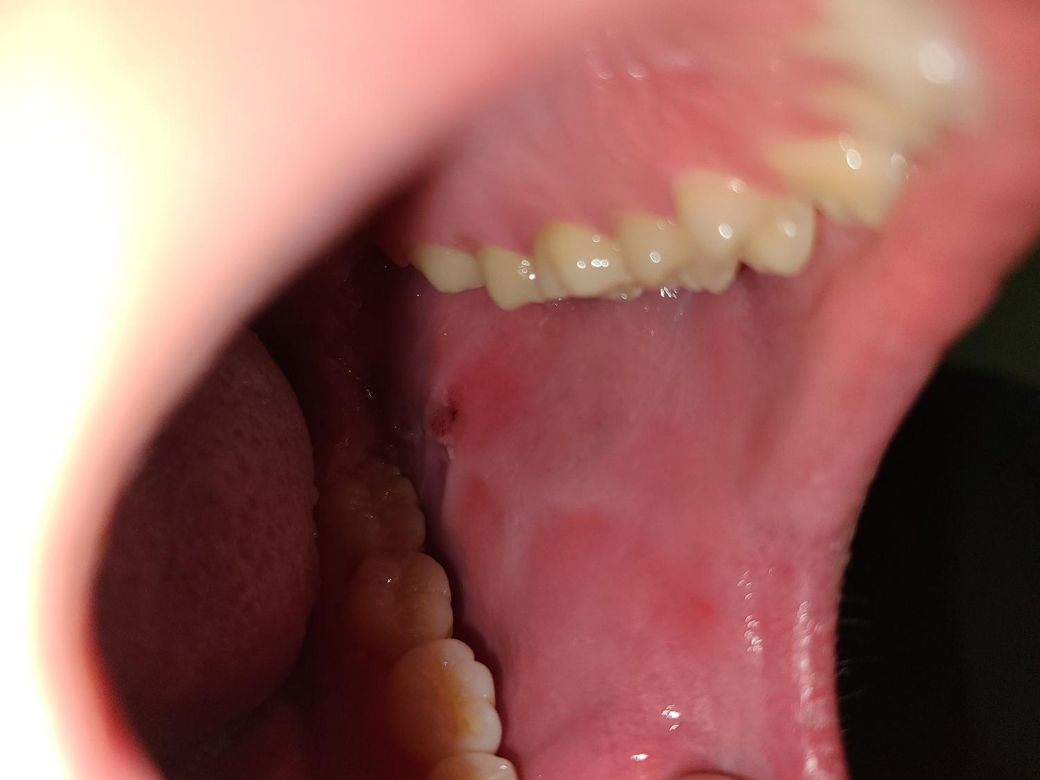

살짝 아파서? 보니까 요래 되어있는데

자다가나 볼을 씹었거나 생활하다가 볼 씹은거겠죠?? 봤는데 이렇게 되어있어서 살짝 걱정되어서 올려봅니다

• 1번 째 사진

볼을 씹은 기억이 없는데 이런 병변이 생기신건가요?

이유없이 이런 병변이 생겼다면 주의가 필요하겠습니다.

만약 해당 부위에 반복적으로 저런 병변이 생긴다면 이비인후과 진료를 받아보시는게 맞겠으며 해당 부위가 낫고는 재발되지 않으면 지켜보셔도 되겠습니다.

볼을 씹었으면 보통 본인이 인지하는 경우가 많습니다. 보통 가벼운 상처는 며칠 내로 자연 치유되지만, 계속 같은 부위를 씹거나 통증과 부기가 심하면 염증이 생길 수도 있으니 조심하는 것이 좋습니다.